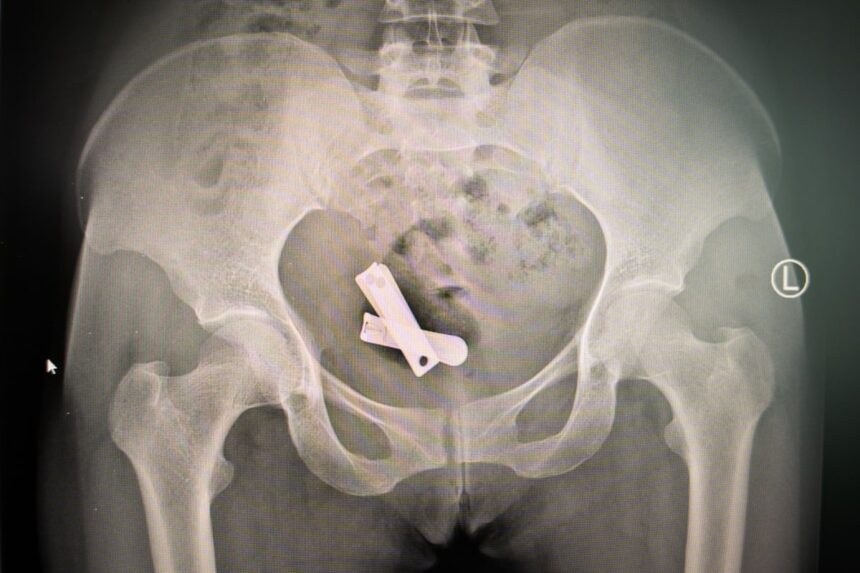

Aceste obiecte, dezvăluite prin raze X și extrase chirurgical de medici la mai bine de doi ani după atac, au fost introduse în Tseneat în timp ce aceasta era inconștientă, după ce a fost violată în grup de șase soldați. Documentele medicale și razele X obținute de o publicație britanică și revizuite de specialiști medicali independenți arată un tipar de cazuri în care femeile au avut corpuri străine introduse în organele lor reproductive, inclusiv cuie, șuruburi, mizerie plastică, nisip, pietriș și scrisori. Conform legislației internaționale, este considerat genocid să distrugi fertilitatea sau să împiedici nașterile cu intenția de a distruge, în totalitate sau parțial, un grup etnic.

Tseneat nu a murit. Timp de șase luni, mama ei a avut grijă de ea. Medicii din zonă nu funcționau, dar știa că ceva era foarte în neregulă: era într-o durere constantă, iar fragmente de plastic și resturi ieșeau ocazional din vaginul ei. A durat aproape doi ani până când Tseneat a căutat ajutor medical. “Eram stresată, aveam un miros urât și celelalte femei nu voiau să stea cu mine. Plângeam afară la clinică. Surorile m-au întrebat: ‘Dacă ești de acord, hai să verificăm uterul tău.’” După ce au îndepărtat materialele vizibile prin colul uterin, personalul a efectuat raze X pentru a verifica dacă există mai multe corpuri străine. Imaginea obținută era greu de înțeles: în centrul uterului lui Tseneat, între oasele șoldurilor ei, se afla o pereche de clești metalici. La momentul extragerii, aceștia erau ruginți, spune sora Roman, care a tratat-o.